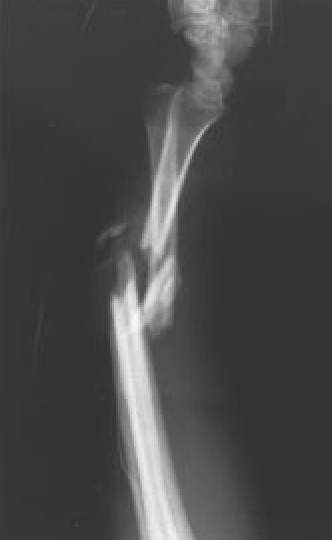

Fig. 4B.: Proyección lateral del mismo caso